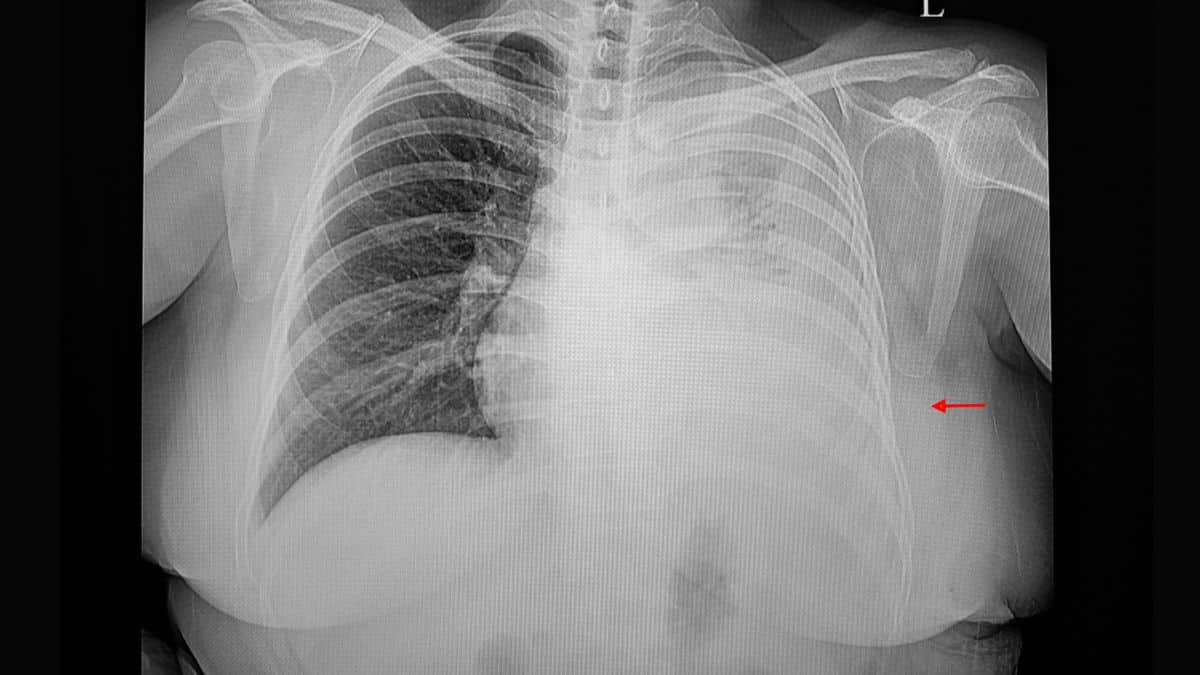

Os sintomas mais comuns, independente do tipo de líquido presente no espaço pleural ou de sua causa, são a dificuldade respiratória e a dor torácica. No entanto, muitos indivíduos com derrame pleural não apresentam qualquer sintoma. Uma radiografia torácica mostrando a presença de líquido é geralmente o primeiro passo para o estabelecimento do diagnóstico. A tomografia computadorizada (TC) mostra mais nitidamente o pulmão e o líquido, e pode revelar a presença de uma pneumonia, de um abcesso pulmonar ou de tumor.